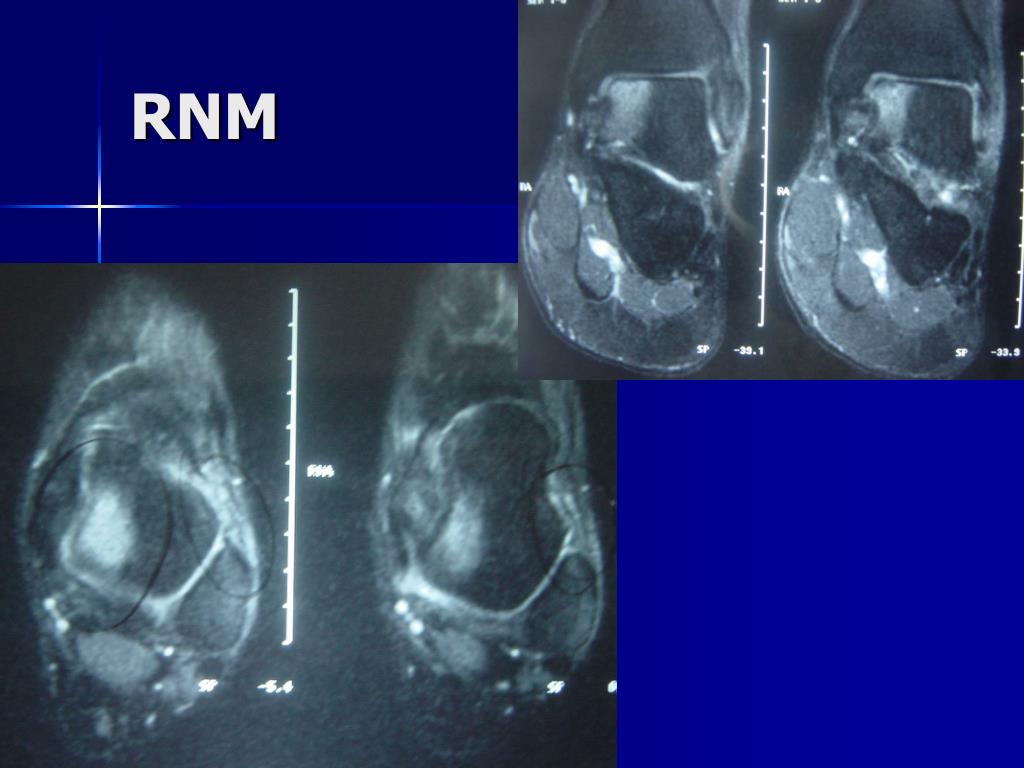

18. RNM

19. DIAGNÓSTICOCLÍNICO X IMAGEM • Exame Clínico: • No Geral= 60% de diagnóstico • Lesão Grau III= 100% • Lesão Grau II= 25% • RNM: • Lesões Associadas • Falta de resposta ao Tto Conservador • Atletas de alto nível Frey, C. – Foot Ankle Int - 1996